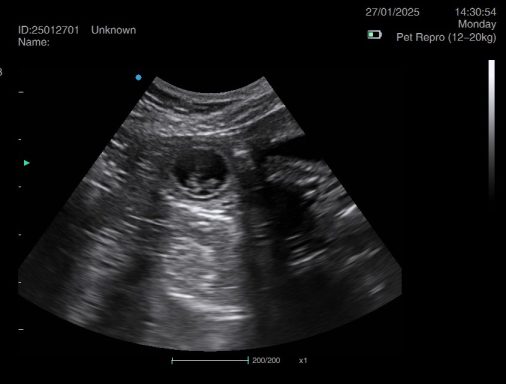

Ultrasound pregnancy scanning is a safe, non-invasive way to confirm pregnancy in dogs and cats, offering breeders and pet owners peace of mind and vital information to support responsible care. It allows us to detect gestational sacs, assess foetal development, and estimate litter size—all while ensuring the wellbeing of the animal.

Pregnancy can sometimes be detected as early as Day 18 post-mating, but scanning at this stage is not routinely recommended. Embryos are still developing and may not be clearly visible, and there is a natural risk of embryo resorption, which can lead to misleading or inconclusive results.

For the most accurate and reliable scan, we advise booking between Day 25 and Day 32, when pregnancy is more easily confirmed and foetal structures are clearer. If an early scan is performed and no pregnancy is detected, we offer a FREE complimentary re-scan after 7 days at the clinic to ensure clarity and support informed decision-making.

Our approach balances early insight with ethical care—always prioritizing the comfort of the animal and the accuracy of the results.